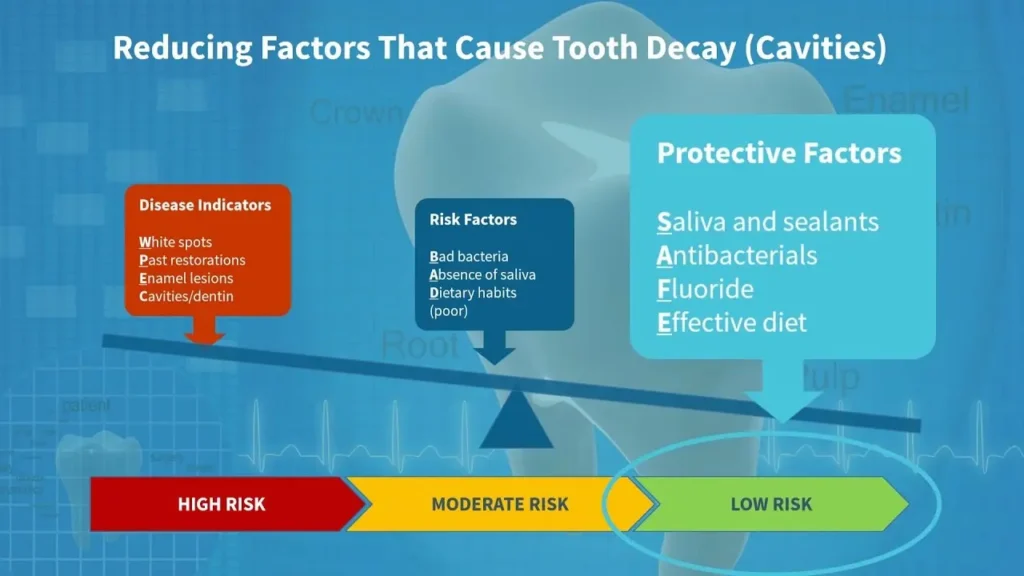

📊 جدول: عوامل افزایشدهنده و کاهشدهنده پوسیدگی دندان

| عوامل خطر | عوامل محافظ |

|---|---|

| مصرف زیاد قند | فلوراید |

| مسواک نزدن | مسواک منظم |

| نخ دندان نکشیدن | نخ دندان روزانه |

| خشکی دهان | بزاق کافی |

| عدم مراجعه به دندانپزشک | معاینه دورهای |

📈 نمودار توصیفی